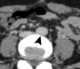

Compression of iliac vein